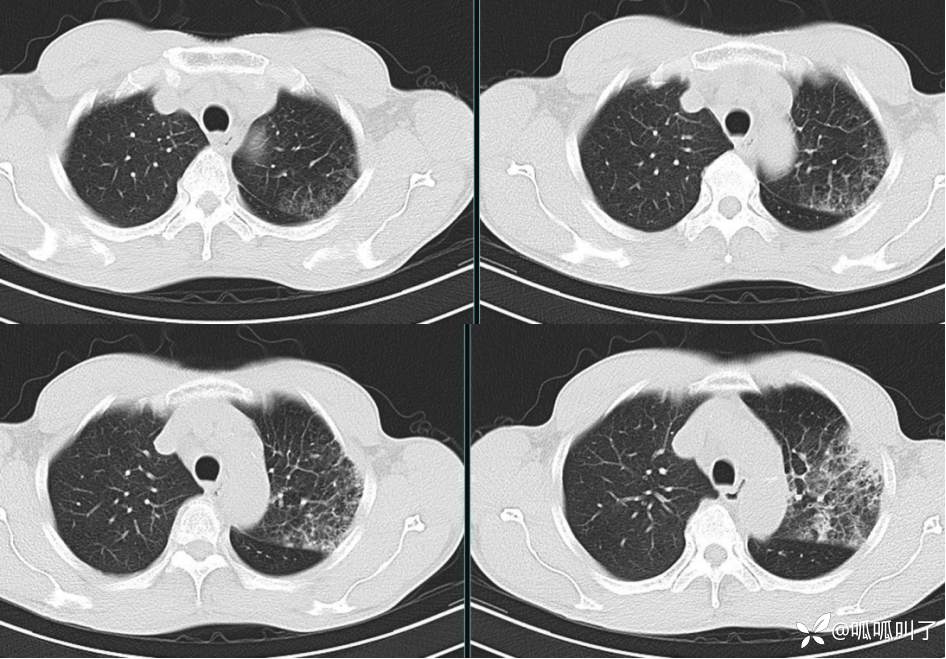

胸部CT平扫和增强: